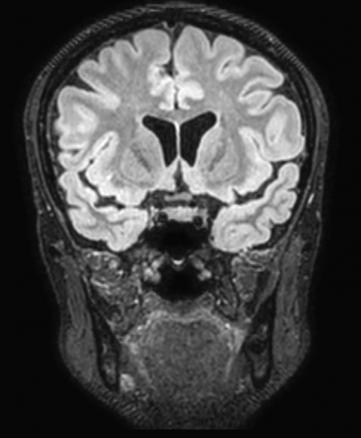

Il s’agit d’une séquence en T2 car la coupe est anti-anatomique : la substance blanche est ici grise et la substance grise est blanche. En temps normal, le liquide cérébro-spinal est blanc (en hypersignal dans les coupes en T2) ; ici, son signal a été supprimé, c’est donc un T2 FLAIR (pour fluid attenuated inversion recovery).